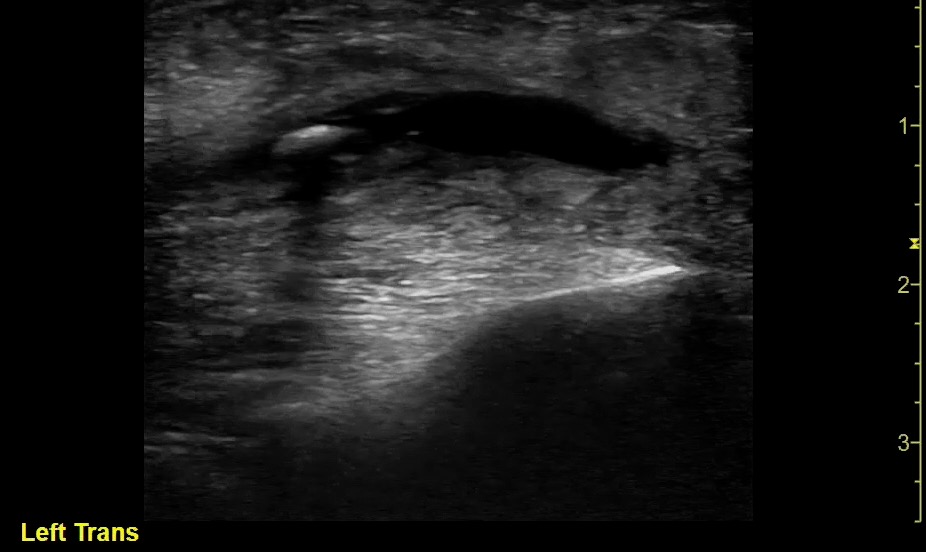

- Figure 15 and 16. Transverse view of normal left parotid gland with color doppler on vessels (1- Retromandibular vein; 2- External carotid artery; 3- Surface of the mandible; 4- Parotid gland; 5- Masseter muscle)

- Superficial and deep lobes divided by plane in which the facial nerve is located, which is superficial to the retromandibular vein and lateral to the external carotid artery.

- Sonographically, the normal parotid and submandibular glands appear homogeneous; the fatty glandular tissue composition causes an increased echogenicity relative to adjacent muscle.

- Parotid Gland:

- Submandibular Gland:

- Triangular in shape with a posterior base.

- More hypoechoic than parotid gland.

- Normal intraglandular ducts are rarely seen on ultrasound.

- The intraglandular ducts are seen as small linear hyperechoic stripes, including the Wharton duct, which emerges from the hilum and passes medially around the mylohyoid muscle. It can be clearly visualized when it is abnormally dilated.